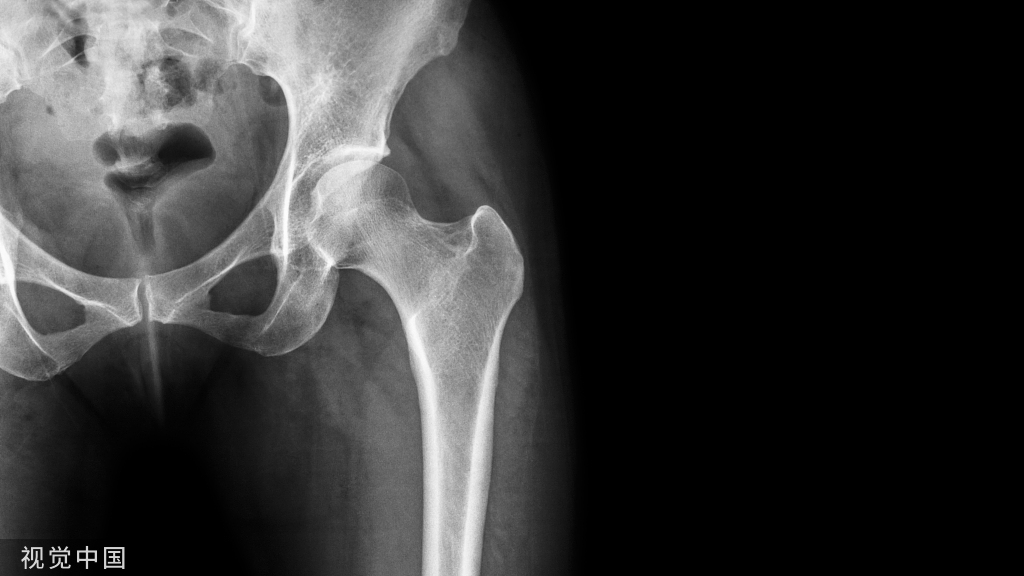

颈干角和膝外翻角:1.颈干角:约127°     2.膝外翻角